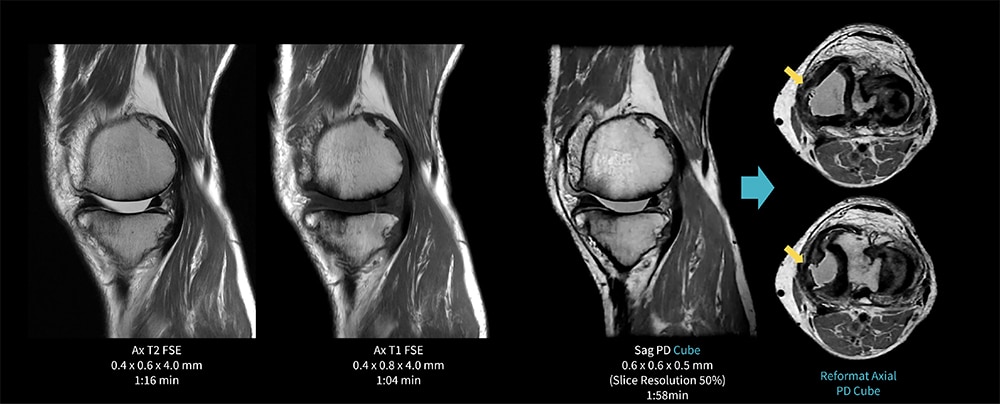

Case9 Cube/変形性膝関節症+内側半月板損傷

80代、男性。変形性膝関節症にてMRI検査を施行した。

膝関節内側の軟骨は著明に菲薄化。内側半月板は大きく関節外方向へ偏位しており、中節に断裂を認める。

AIR Recon DLを併用した3D PD Cubeは短時間撮像でもMPRで観察可能である。

図9 Cubeを用いた膝関節検査